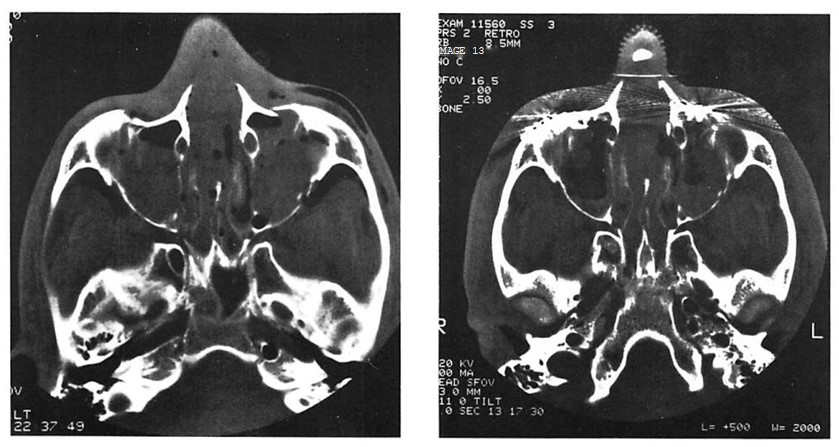

Fig 4. Highly comminuted fracture of supraorbital portion of large frontal sinus that extends to lateral orbit treated with open reduction and microplate and screw fixation. (A) Preoperative axial computed tomographic (CT) scan. (B) Postoperative axial CT shows stable reduction 2 months after injury. Note symmetrical contour of frontal soft tissues.

Fig 4. Highly comminuted fracture of supraorbital portion of large frontal sinus that extends to lateral orbit treated with open reduction and microplate and screw fixation. (A) Preoperative axial computed tomographic (CT) scan. (B) Postoperative axial CT shows stable reduction 2 months after injury. Note symmetrical contour of frontal soft tissues.

In this series only 1 patient had clinically apparent loss of fracture reduction in the area stabilized by microplates (see Fig 4). Of the 42 patients, 23 had CT scans in the early postoperative period and, with the exception of the patient presented in Figure 4, revealed near anatomical reduction of their fractures. There were 2 patients who required secondary surgery to improve globe position as a result of inadequate initial internal orbit reconstruction.

The patient presented in Figure 4 also had an open wound with extensive soft tissue injuries that were sutured in the emergency room. The patient developed extensive necrosis of the tem-poralis requiring debridement and intravenous antibiotic therapy. Six weeks later this patient presented with orbital cellulitis. Debridement at this time revealed further muscle necrosis and loose microfixation hardware, which was removed and replaced with miniplates after appropriate debridement. A secondary reconstruction was performed 6 months after the initial surgery without incident.